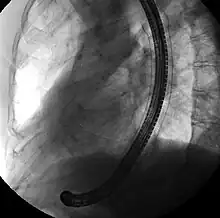

Fluoroscopic image of self-expandable metallic stent in the esophagus. The black solid structure is the endoscope used to place the stent.

Esophageal SEMS are placed after a gastroscopy is performed to identify the area of narrowing. The area may need to be dilated to allow the gastroscope to pass.[14] The tumour is usually better seen with the direct vision of endoscopy than on a fluoroscopic image. As a result, radio-opaque markers are usually placed on the surface of the patient to mark the area of narrowing on fluoroscopy. The SEMS is placed through the channel of the endoscope into the esophagus over a guidewire, marked on fluoroscopy, and mechanically deployed (using a device that sits outside of the endoscope) such that it expands when in position. Hypaque or other water-soluble dye may be placed through the passage to ensure patency of the stent on fluoroscopy.[15] Enteric and colonic SEMS are inserted in a similar fashion, but in the duodenum and colon respectively.[16]